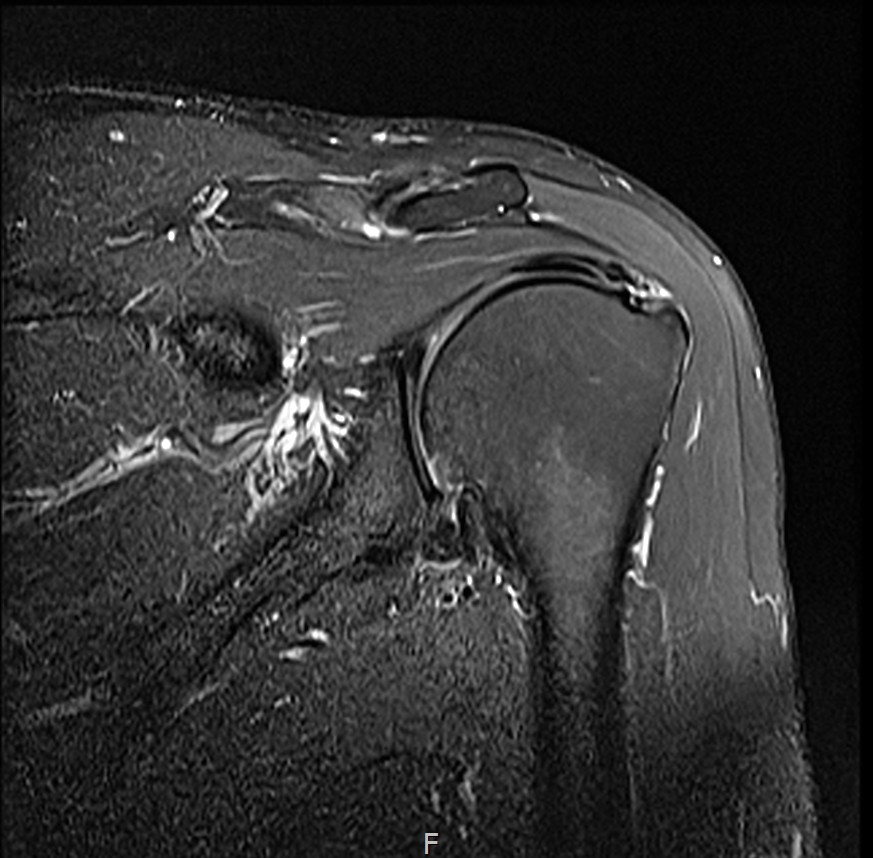

6개월 후 MRI: 인대 두께 5.8mm (1.6mm 증가)

통증 소실

수영 복귀 (접영 제외, 자유형 위주)

6개월 후 MRI: 인대 두께 6.2mm (1.7mm 증가)

파열 부위 재생 확인

크로스핏 복귀 (오버헤드 동작 주의)